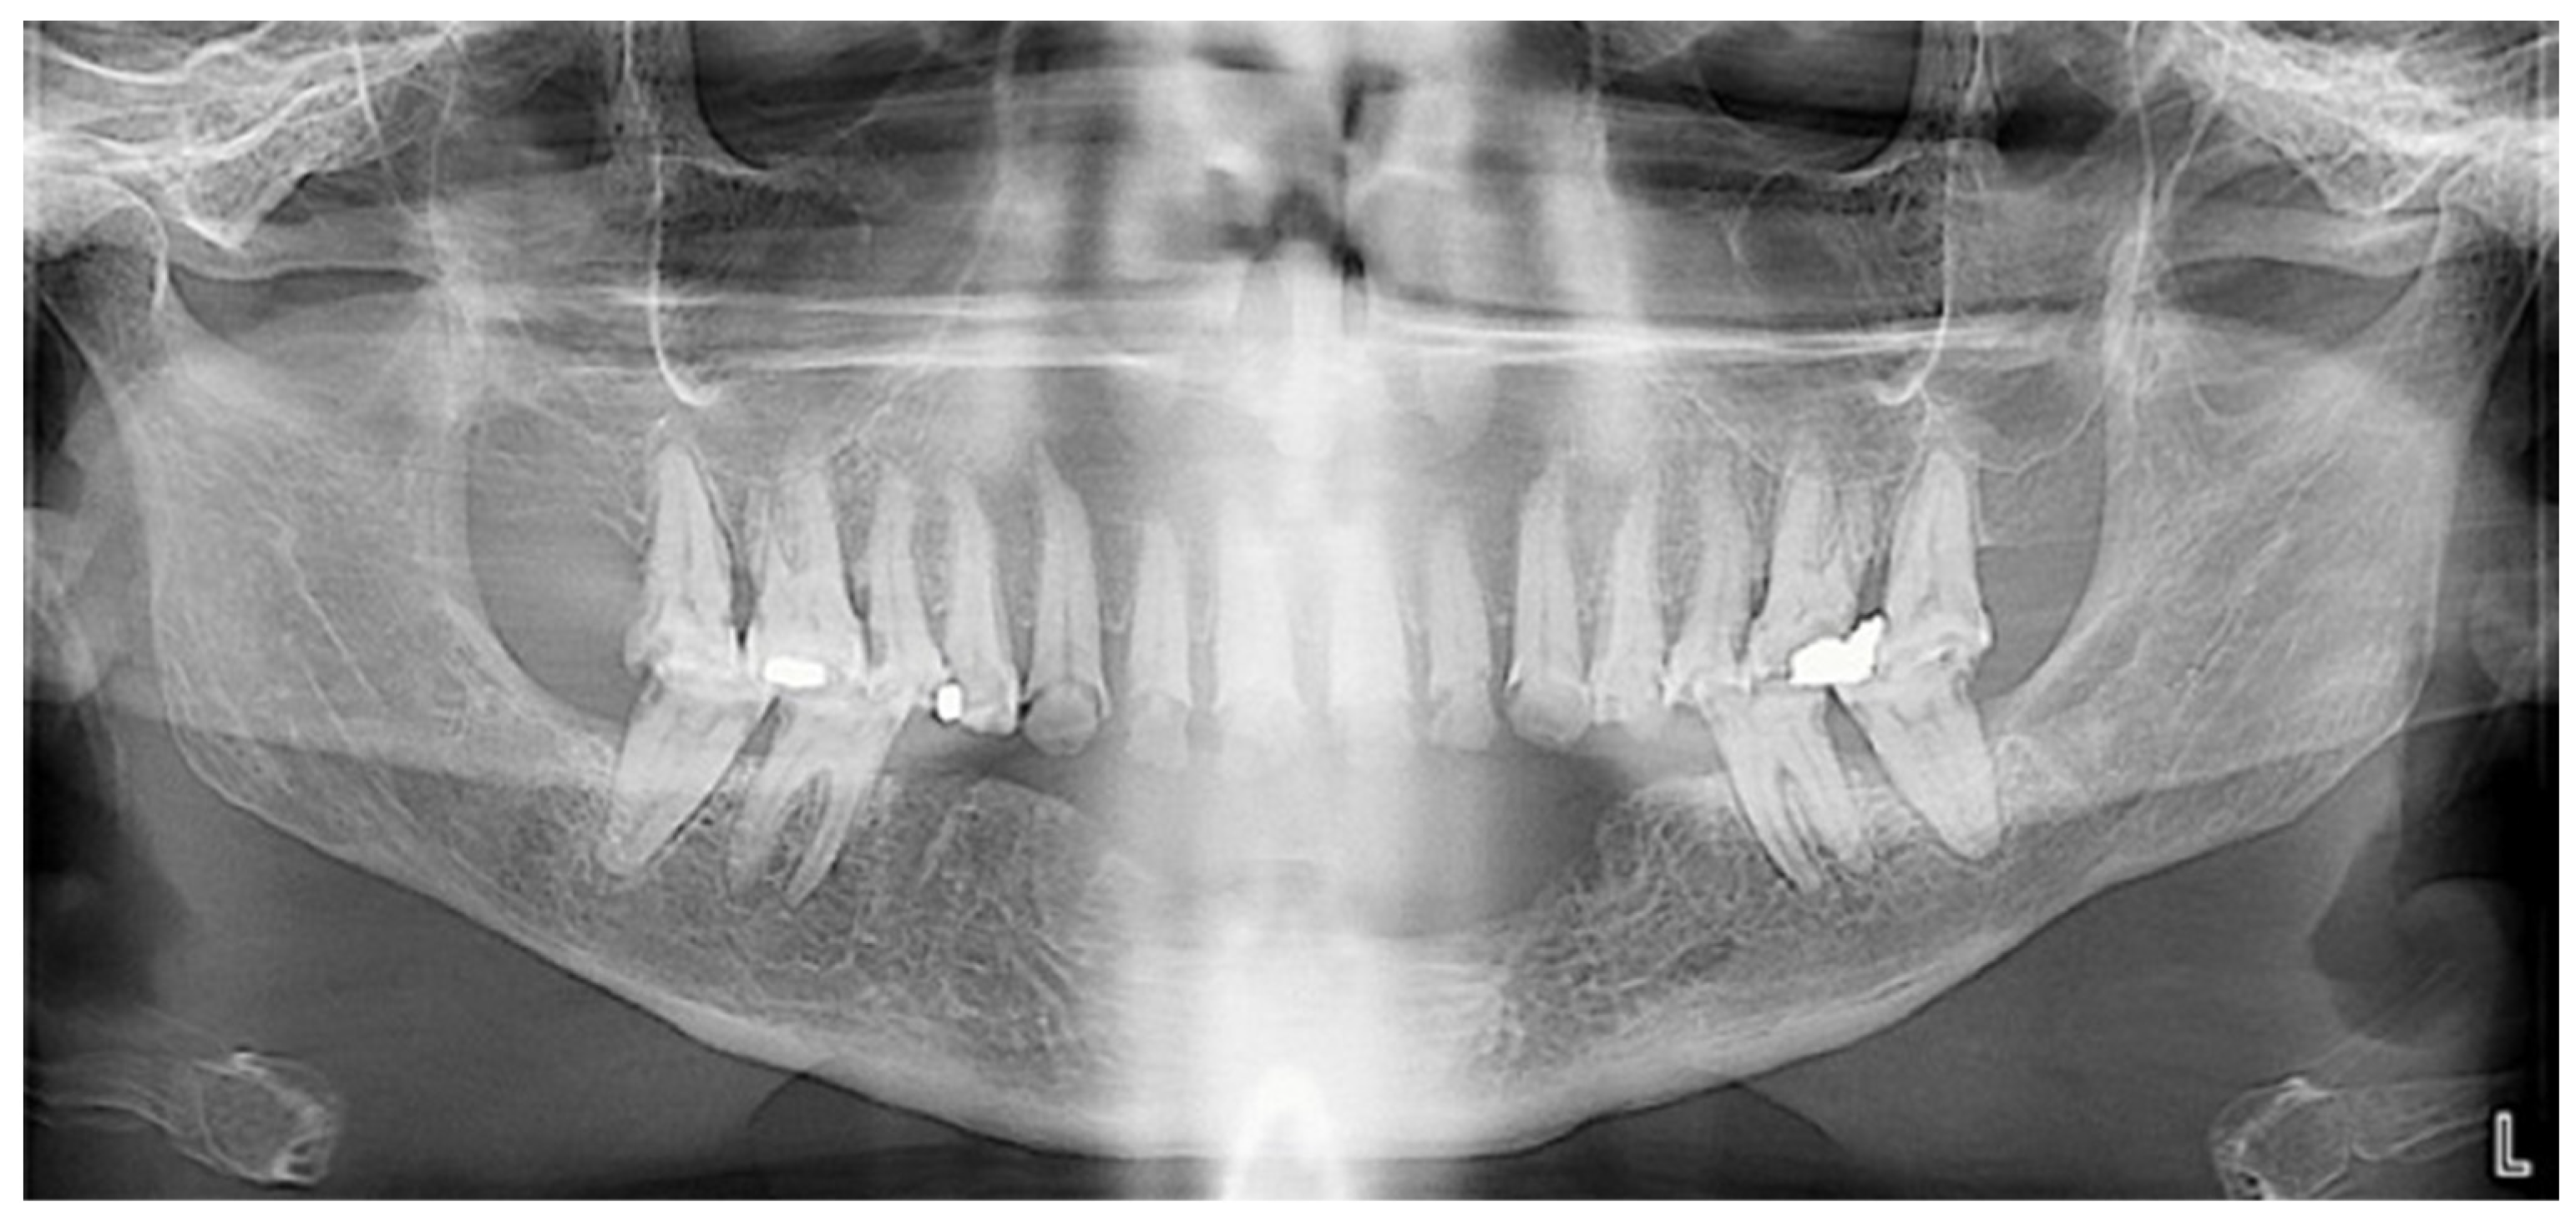

2.2. Clinical History and Diagnostic Assessment

2.4.1. Step 1: Diagnostic Set-Up and Provisional Prosthesis

2.4.2. Step 2: Pre-Prosthetic Treatment Under General Anesthesia

- First GA session (March 2023, lasted 3 h and 30 min): Pre-prosthetic care for mandibular teeth.

- Second GA session (June 2023, lasted 3 h and 30 min): Pre-prosthetic care for maxillary posterior teeth, and non-traumatic extractions of teeth 17 and 26.

- Third GA session (June 2023, lasted 2 h and 30 min): Pre-prosthetic care for maxillary anterior teeth [9].